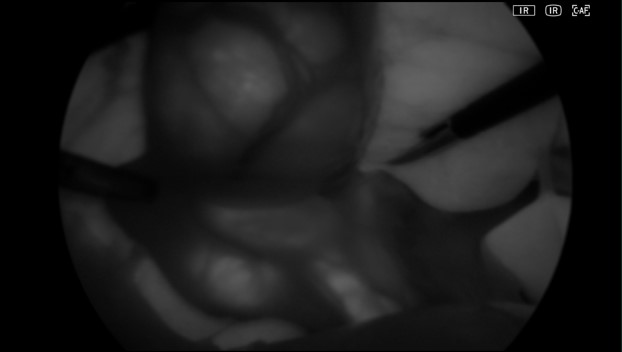

白色重畳IR→IR+マゼンタ→IR単独(白黒)

• IR+マゼンタ

• IR単独(白黒)

• 10mm硬性鏡を使用した臨床動画